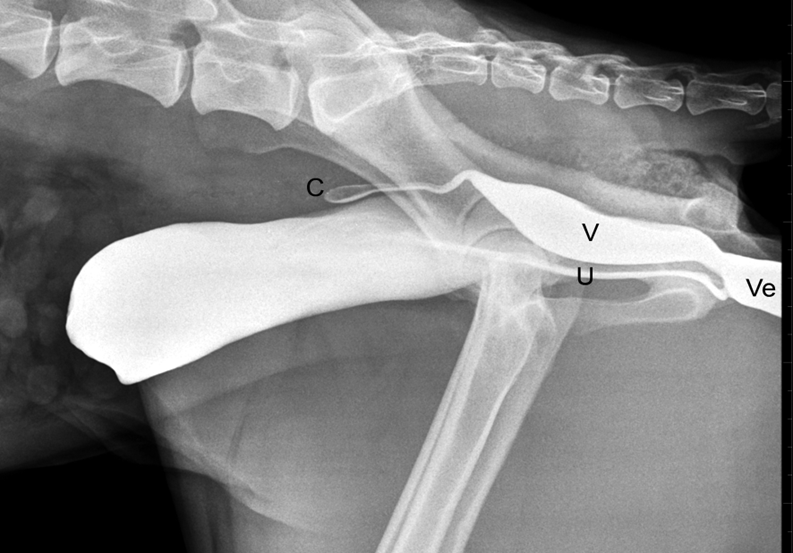

What is being shown here after the use of Intravenous Urography?

Ectopic ureter —> the ureter is dilated and is inserting into the urethra rather than the trigone of the bladder